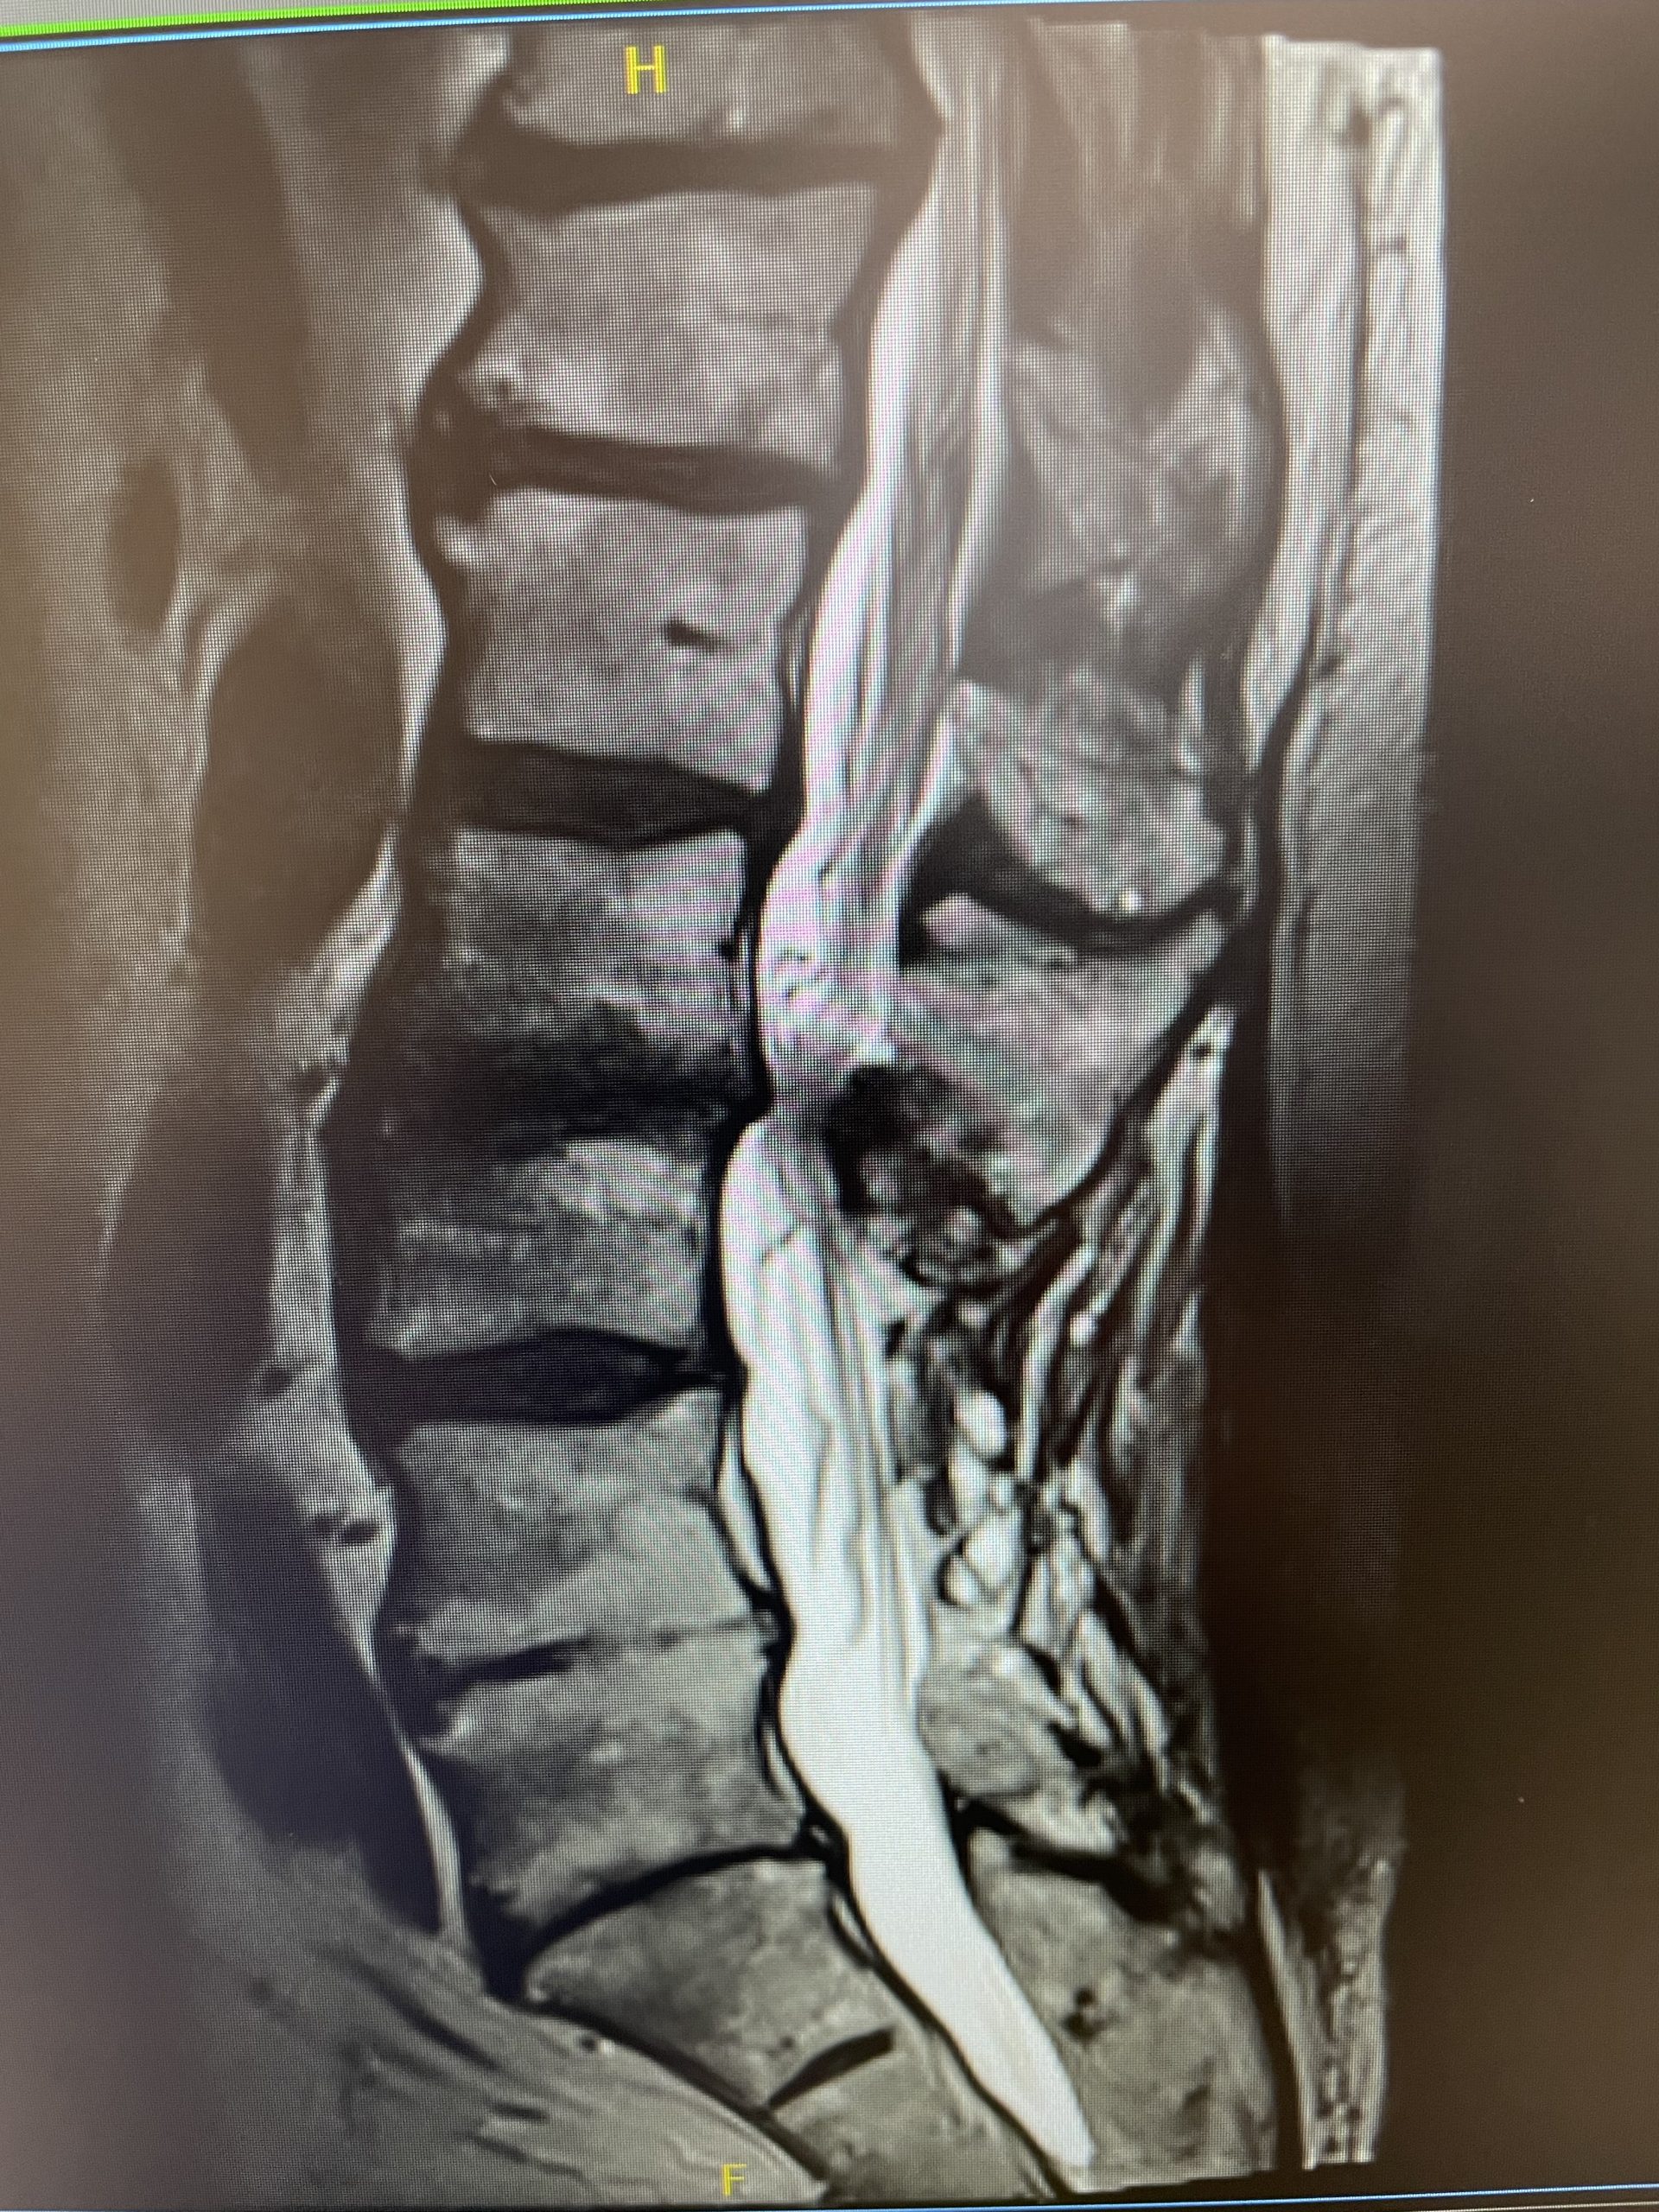

A 35-year-old female presents with severe low back pain and progressive left leg pain. She had initially presented nine months prior with mainly low back pain with mild left leg symptoms. She had an MRI (Fig 1) demonstrating a transitional L5 lumbar vertebra. This L5 vertebra is sacralized in that it is more anatomically associated with the sacral level with a rudimentary disc between it and the segment below. Because of the rudimentary disc there is very little movement at that level, hence more stress is put on the segment above.

As a result, the patient has developed severe degenerative disc disease with collapse and a retrolisthesis above. There is also a left sided disc osteophyte complex that is causing foraminal stenosis and mild thecal sac compression. Up to this point, the patient had failed all means of conservative management including physical therapy, epidural injections, and medicine. Because of the current worsening of left leg pain another MRI was performed which demonstrated a significant increase in the disc herniation with severe thecal sac compression and nerve root compression (Fig 2). It was decided to schedule the patient for decompression, discectomy, and fusion because of the progression of disc herniation and retrolisthesis.